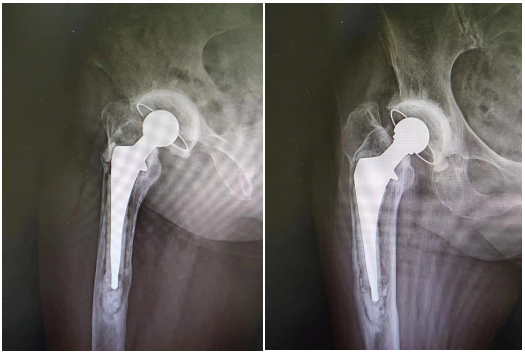

骨科副主任王建伟门诊查体并进行髋 DR 检查发现,患者右侧人工髋关节假体周围骨溶解严重,假体下沉松动。于是骨科团队考虑患者疼痛为人工髋关节置换术后假体松动所致,要想彻底治愈只能做翻修手术。

3 月 8 日,由骨科副主任王建伟主任医师主刀,李延明副主任医师、蔡文龙主治医师、杨志军住院总医师为助手,髋关节翻修手术历时 3 小时按照术前计划顺利完成。术后拍患肢 X 光片提示翻修假体型号、位置良好,完全纠正了术前患肢的短缩畸形。